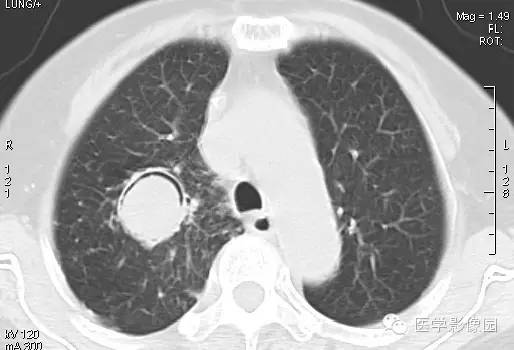

CT表现

右肺内见一圆形空洞病灶,内有圆形曲菌球,边缘光滑,可随体位改变而变动,曲菌球与洞壁之间可见“新月征”。